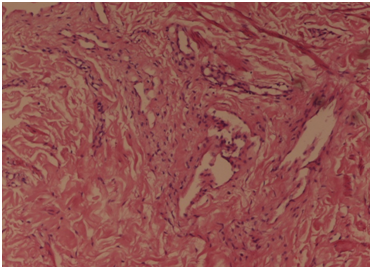

A 19-year-old female student visited the outpatient gynecology clinic with complaints of pruritus vulvae for 3 years. The itching was intense enough to wake up the patient at night. She denied of any vaginal discharge and was not sexually active. She also had history of chronic rhinitis. She took treatment off and on in the form of topical and systemic antibiotics, antifungals, antihistaminics and steroids, but was not relieved although the patient reported spontaneous remissions. Physical examination revealed a 0.5 x 1 cm dry patch on her vulva. There were no nodules present either on the vulva or anywhere on the body. As the patient had already taken treatment for 3 years without any relief, so a decision for vulval biopsy from the identified patch was taken. Histopathological examination showed hyperkeratosis with focal epithelial hyperplasia and mild mononuclear infiltrate in upper subepidermal region with fibrocollagenous stromal dermis. (Figure 1). There was marked degree of hyperplasia of cutaneous nerves and neuroid structure with collagenization of the dermis (Figure 2). No other specific pathology was noted. S-100 immunostain revealed an increase in number and size of cutaneous nerves throughout the dermal zone. She was prescribed topical emollients and corticosteroids along with habit reversal therapy and was referred to a dermatologist.

Figure 1 Histopathological examination showed hyperkeratosis with focal epithelial hyperplasia and mild mononuclear infiltrate in upper subepidermal region and firbrocollagenous dermis. Hematoxylin and Eosin x 10X.